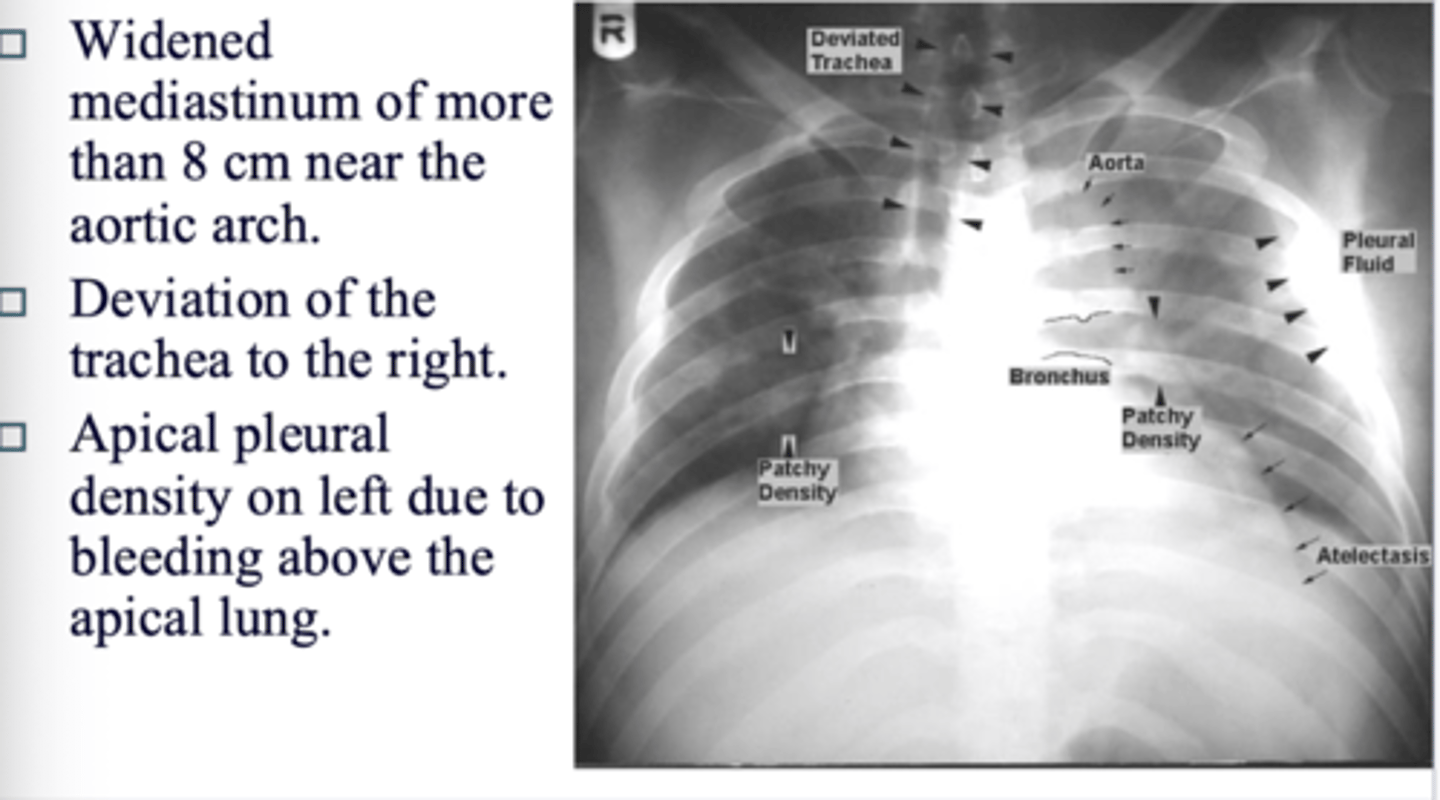

What are the signs of a tear on CT?

◼ Widened mediastinum of more than 8 cm near the aortic arch.

◼ Deviation of the trachea to the right.

◼ Apical pleural density on left due to bleeding above the apical lung.

<p>◼ Widened mediastinum of more than 8 cm near the aortic arch.</p><p>◼ Deviation of the trachea to the right.</p><p>◼ Apical pleural density on left due to bleeding above the apical lung.</p>